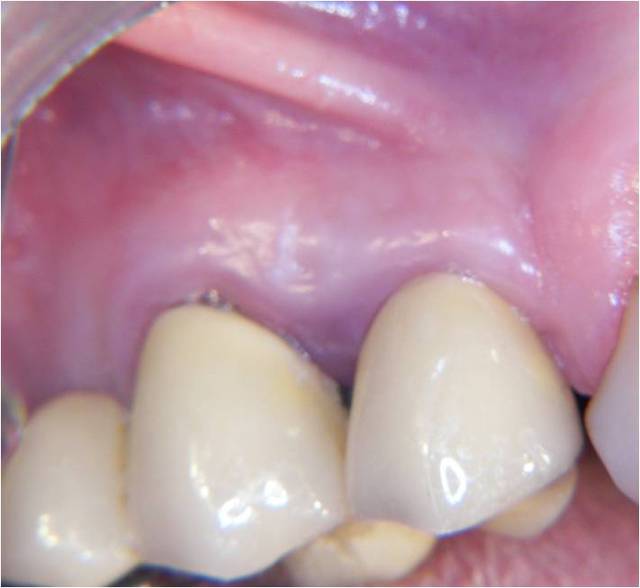

étude du scan et plutôt que les forets, ostéotomes (manuels, impactés) et ou spreader (messinger, MIS, ou autres) la corticale du sinus se sens en général et tu pourras la longer sans effraction (encore que dans ce cas, ça s’appelle un Summers et ça marche fort bien.

exemple un D2 Tatum posé en 90 (à l'époque pas de scann...donc reflexion sur le pano et visualisation 3 D dans la tête...surtout dans celle du patient.

la photo est de 2012